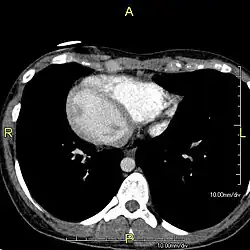

Zespół Kartagenera (ang. Kartagener’s syndrome) stanowi około połowy przypadków chorych z pierwotną dyskinezą rzęsek; w zespole tym, opisanym po raz pierwszy w 1904 roku, występuje klasyczna triada objawów, zwana triadą Kartagenera: zapalenie zatok przynosowych (sinusitis), rozstrzenie oskrzeli (bronchiectases) i odwrócenie trzewi (situs inversus). Postuluje się wpływ nieprawidłowej funkcji rzęsek w patogenezie zaburzenia embriogenezy, jakim jest situs inversus. Nazwa zespół nieruchomych rzęsek stosowana wcześniej wymiennie z terminem pierwotnej dyskinezy rzęsek nie powinna być używana, ponieważ nieprawidłowo zbudowane rzęski posiadają zdolność do ruchu; nie wystarcza ona jednak aby nabłonek urzęsiony mógł prawidłowo pełnić swoją funkcję.

- klasyczna triada: zapalenie zatok, rozstrzenia oskrzeli i situs inversus występuje w około 50% przypadków i stanowi podstawę rozpoznania zespołu Kartagenera